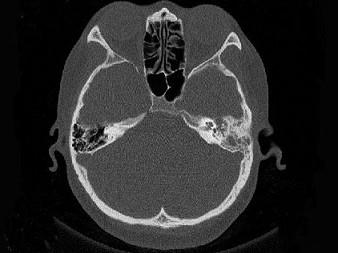

问题 女,34岁,左耳鸣,听力下降两个月,PE:左外耳道有脓性分泌物,鼓膜充血水肿,左中耳腔内软组织影,CT检查如图,最可能诊断为 ( )

选项 A、肉芽肿形成 B、中耳结核 C、中耳癌 D、胆脂瘤 E、乳突癌

答案 A